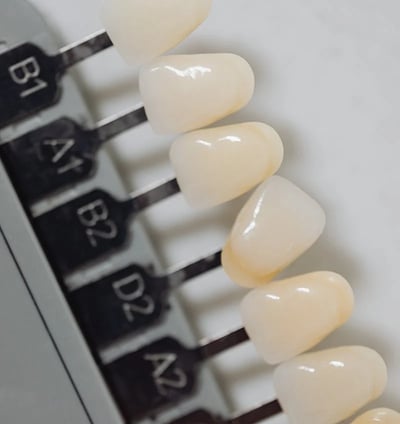

Stomatologie estetica

Albire dentară cu laser, fațete dentare și restaurări cosmetice pentru un zâmbet radiant.

Protetică dentară:

Refacerea dinților lipsă sau deteriorați prin coroane, punți și proteze adaptate nevoilor fiecărui pacient.